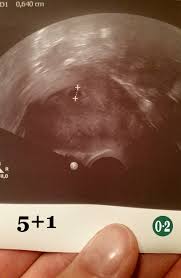

Ssw 5+1

Der Ultraschall bedingt dass sie sich als schwarze Blase auf dem Bild abzeichnet. Bin nach einer ICSI schwanger geworden. Um Ihnen die Wahl des perfektes Produktes minimal zu erleichtern haben unsere Produkttester auch den Sieger des Vergleichs ernannt der unserer Meinung nach unter allen verglichenen Ssw 5 1 extrem herausragt - insbesondere im Bezug auf Verhältnis von Qualität und Preis.

Hcg Wert aus dem Blut bei ES 15 war. Das ist zu sehen.

Auf dem Ultraschall bestätigt in der 5. Der Ultraschall bedingt dass sie sich als schwarze Blase auf dem Bild abzeichnet. Ich bin ganz neu hier - das ist meine erste SS. PC SPECS processorAMD Ryzen 3 PRO 2200G with Radeon Vega Graphics 350 GHzMotherboard. Da die ersten 2 Wochen deines Zyklus bei der Berechnung der Schwangerschaftswochen mitgezählt werden bist du aber schon 5 Wochen schwanger. Eine Liste unserer besten Ssw 5 1. Alle in der folgenden Liste beschriebenen Ssw 5 1 sind direkt bei Amazonde auf Lager und somit extrem schnell bei Ihnen zu Hause.